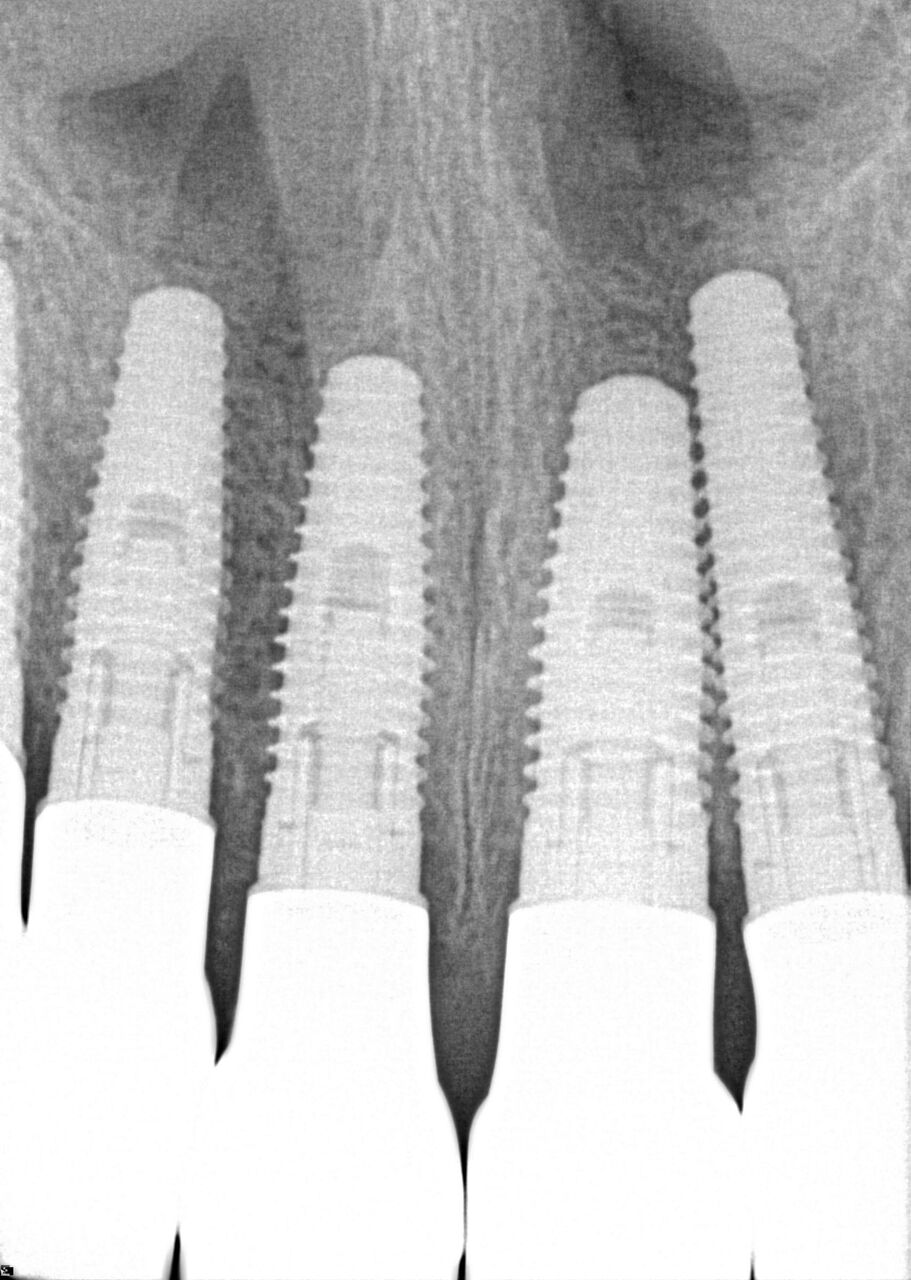

(20.) 6-month integration confirmation of Nos. 6 through 10.

Figure 20

(21.) 6-month integration confirmation of Nos. 6 through 10.

Figure 21

A 42-year-old man presented with a very loose bridge on Nos. 6 through 9 with periodontally compromised retainers on Nos. 6 and 9 (Figure 17 through Figure 19), and endodontically involved No. 10 with a calcified canal. Teeth Nos. 6, 9, and 10 were extracted, the sockets fully debrided, and pontic soft tissue on Nos. 7 and 8 sculpted to be symmetrical in soft tissue contour with the contralateral lateral incisor and central incisor locations. Implants were secured in position Nos. 6 through 10 (Figure 20) in excess of 45 Ncm, the bone was milled to provide unimpeded seating of temporary abutments, and temporary crowns were fabricated chairside and adjusted to be out of occlusion in centric relation and all excursions. The temporary crowns were cemented after extrusion of excess cement extraorally and the patient was prescribed antibiotics, analgesics, and instructed in postoperative care particular to immediately provisionally restored implants. At 6 months, integration was confirmed (Figure 20 through Figure 23) and after placement of scanning abutments, the implants and soft tissues were scanned. Final crowns were fabricated from the scanned images and were cemented after extrusion of excess cement extraorally (Figure 24 through Figure 26), and oral hygiene procedures were reviewed.